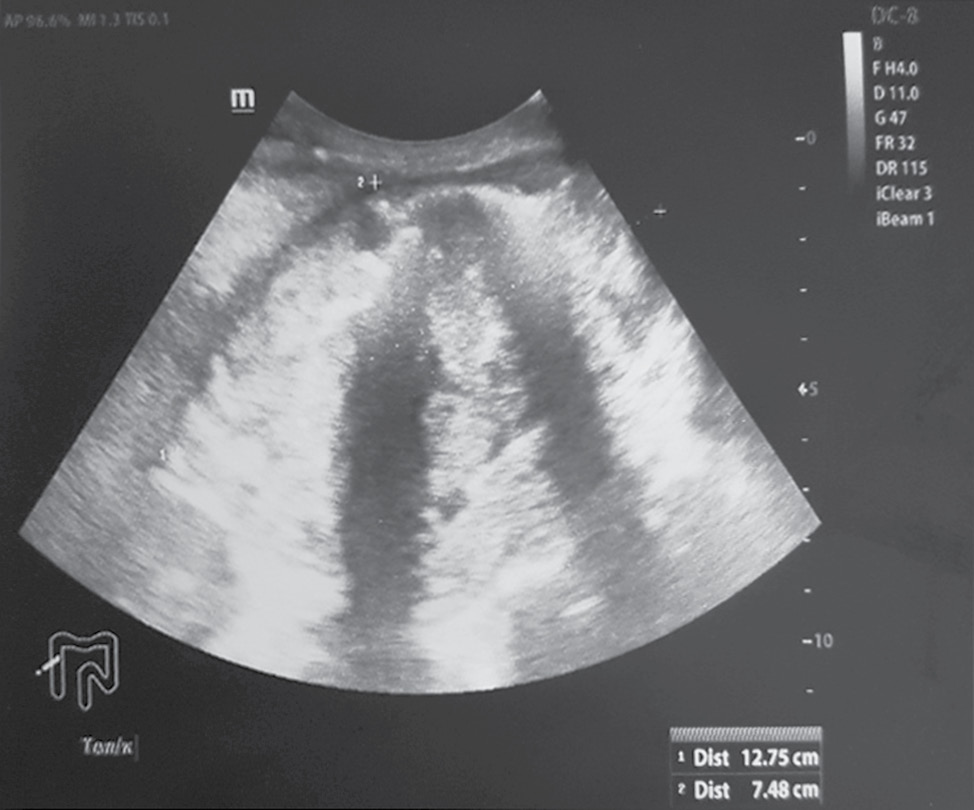

Отграниченное скопление жидкости в области инфильтрата визуализировано у 3 (5,5 %) пациентов, свободная жидкость в брюшной полости обнаружена у 2 (3,6 %) больных. Кроме того, УЗИ позволяло выявить метастатическое поражение печени, стадировать процесс, что в некоторой степени также влияло на тактику ведения пациентов. Существенную роль в выявлении перифокального воспаления при отсутствии клинической картины играла спиральная компьютерная томография. Утолщение стенки кишки с неравномерным, достаточно часто циркулярным сужением просвета в сочетании с тяжистостью, уплотнением окружающей ткани позволяли достаточно достоверно диагностировать ПФВ. Появление газа в параколярной клетчатке свидетельствовало о формировании параканкрозного абсцесса или перфорации опухоли (рис. 3).

Рис. 3. Опухоль ректосигмоидного отдела толстой кишки, осложненная перифокальным воспалением с формированием паратуморозного абсцесса

Fig. 3. Colorectal rectosigmoid tumor complicated by perifocal inflammation with the formation of pratumor abscess